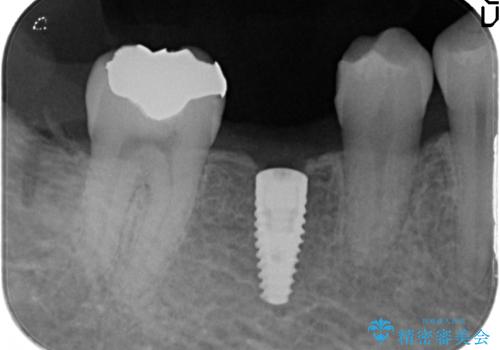

- 右下の奥歯にインプラントを入れたいと来院。

抜歯から時間が経っており、骨が十分あったためすぐにインプラントを入れることが可能でした。骨も補う必要がありませんでした。

手術が怖いとのことで、外科手術時には静脈麻酔を行い、眠っている間に手術が終わるようにしました。

インプラントの術式は比較的単純で、難しくないですが、予後を見据えて角化歯肉を増やす手間をかけることが大変重要です。

- 52万円 内訳:ストローマンインプラント(1本)42万円(仮歯、ジルコニアクラウン、カスタムアバットメント含む) 静脈麻酔 5万円x2回費用は治療当時の料金となります

インプラント手術時に同時に親知らずの抜歯も行い、腫れや痛みなどを1度で終わらせるようにしました。